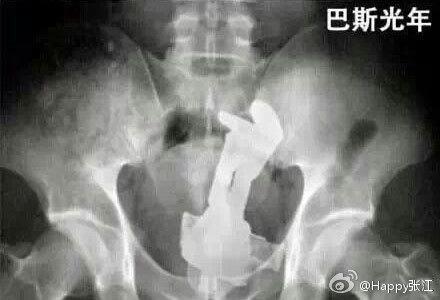

据说这是医生们盘点的肛门塞入东西的奇葩之最,毁三观啊